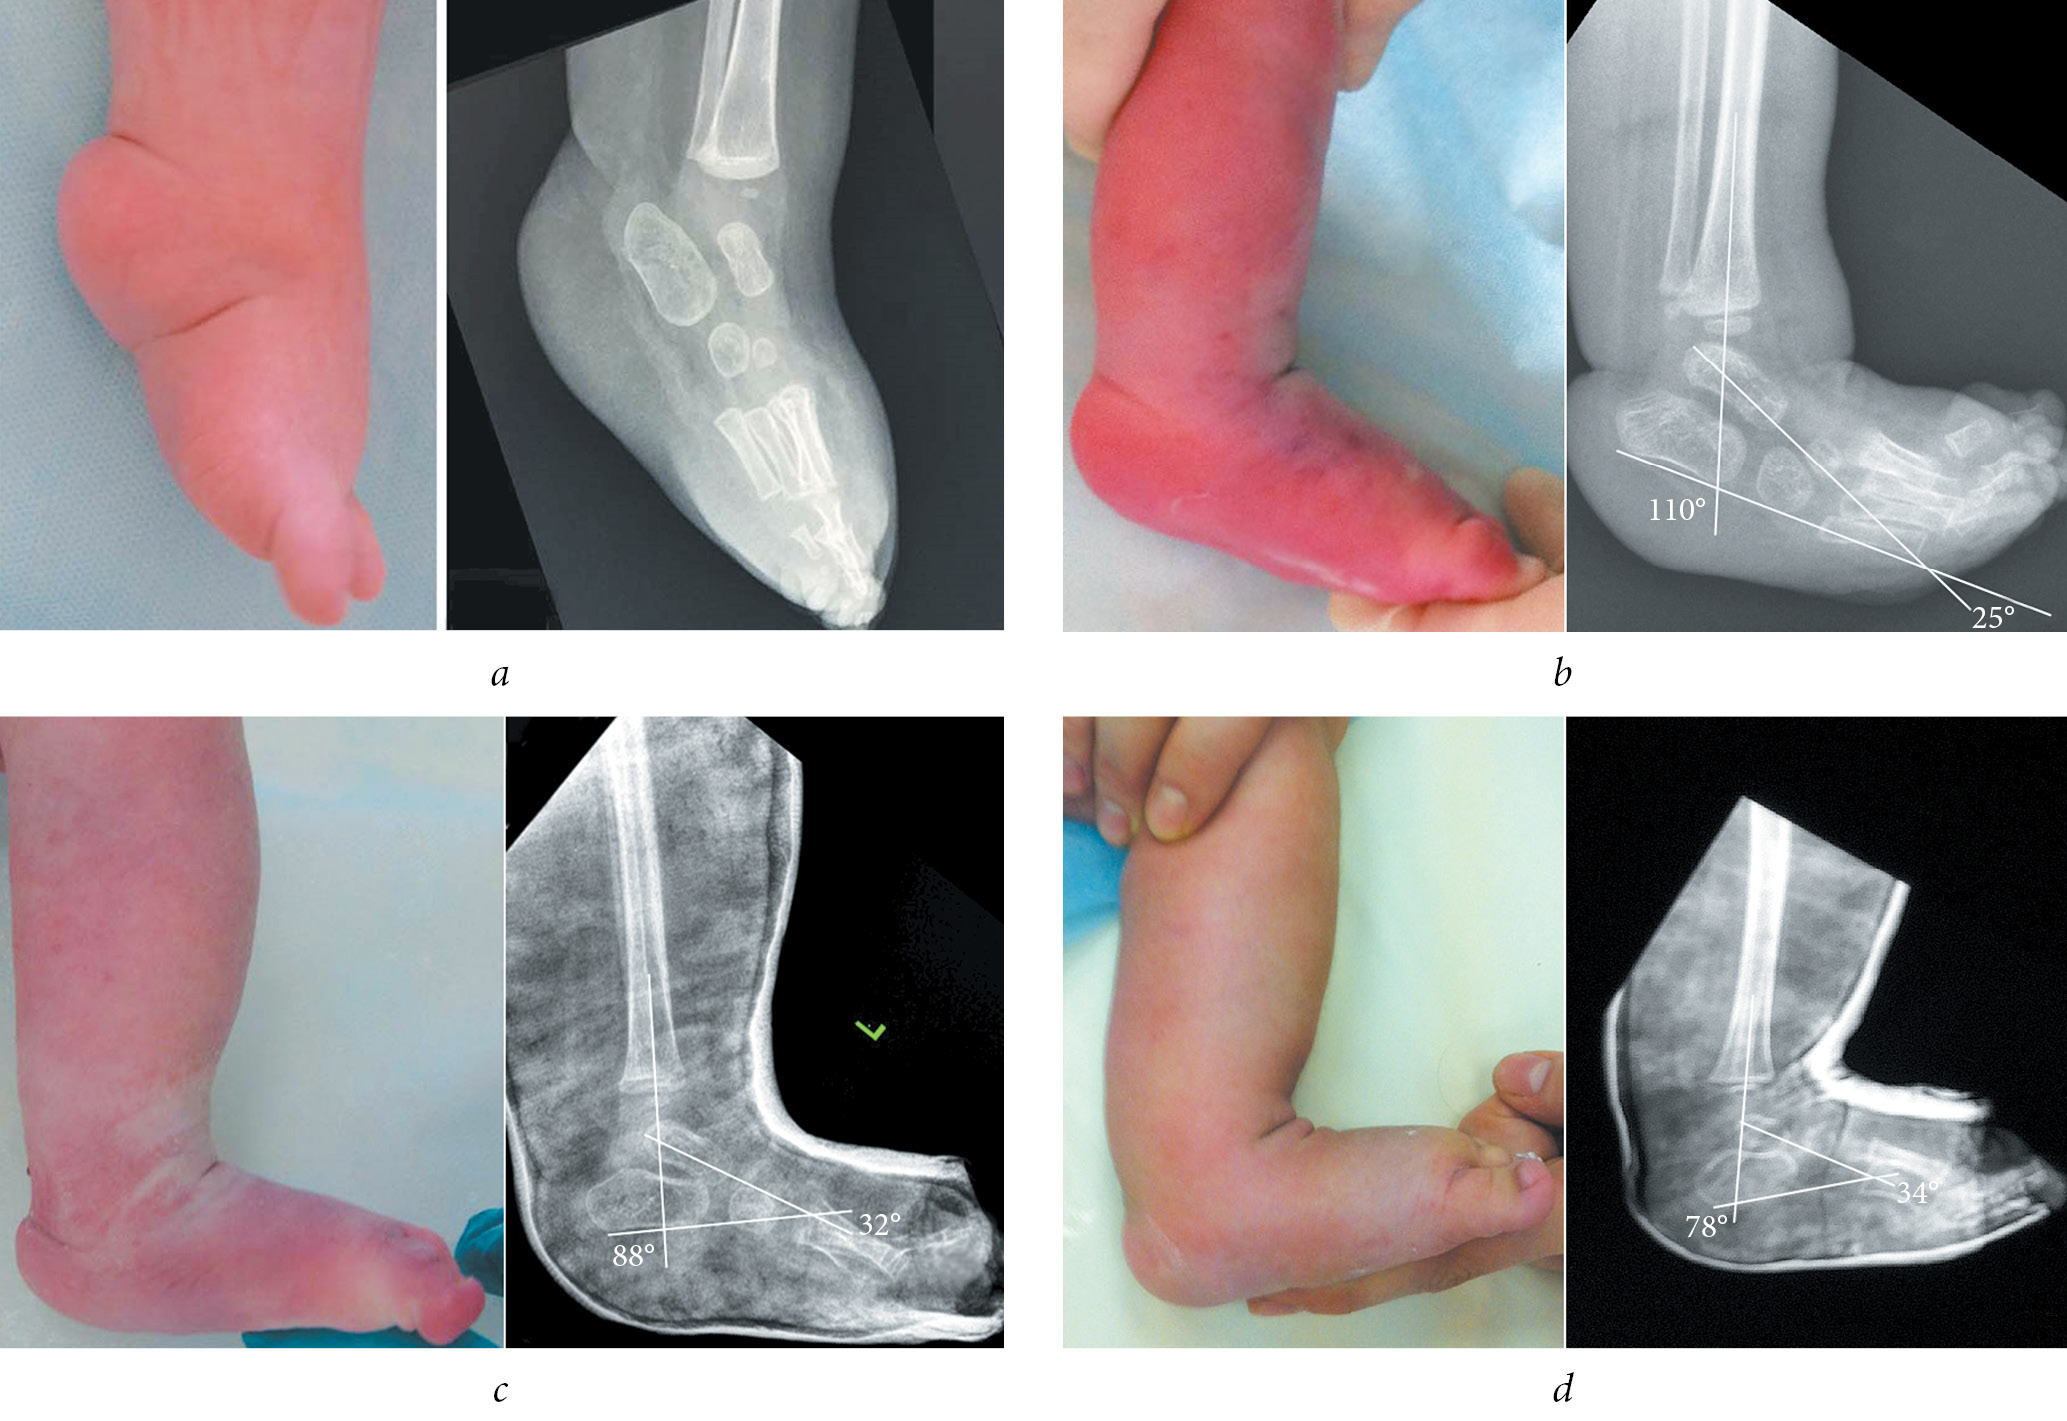

Radiography of the feet was performed in all pediatric patients before and after achillotomy and after plaster cast removal, in two standard views, namely, antero-posterior and lateral in the position of maximum dorsal flexion. After achillotomy, radiography of the feet was performed in a plaster cast immediately after manipulation. Radiographs were analyzed by evaluating the astragalocalcanean angle and astragalocalcanean and calcaneotibial angles in the antero-posterior and lateral views, respectively (Fig. 1).

Fig. 1. Radiograph of the foot of a 5-month-old infant: a — antero-posterior view: astragalocalcanean angle of 34°; b — lateral view: calcaneotibial angle of 90° and astragalocalcanean angle of 35°